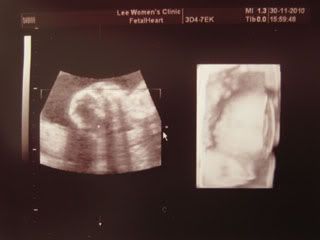

Her face.